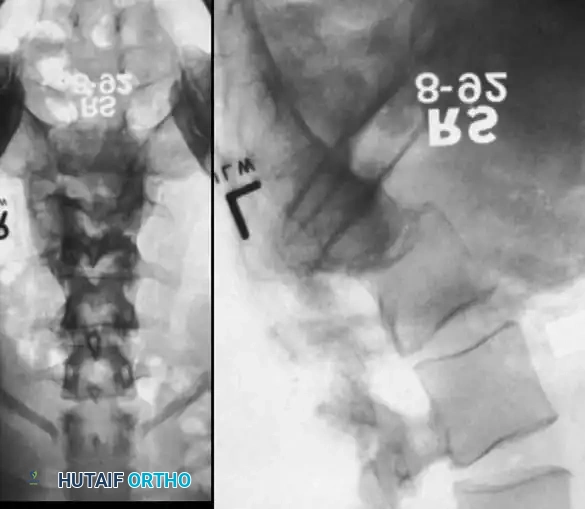

Severe Lumbosacral Deformity: The L5 Vertebrectomy

In cases of extreme lumbosacral kyphosis or spondyloptosis associated with myelomeningocele, a standard fusion is insufficient to restore sagittal balance. Gaines described a powerful two-stage L5 vertebrectomy technique to address this.

Stage 1 (Anterior): The L5 vertebral body and adjacent discs are completely excised via an anterior approach, decompressing the anterior neural elements and mobilizing the spine.

Stage 2 (Posterior): The patient is flipped prone. The L4 vertebra is then reduced directly onto the sacrum (S1), effectively shortening the spine, correcting the kyphosis, and allowing for rigid posterior pedicle screw fixation from the lumbar spine to the pelvis.